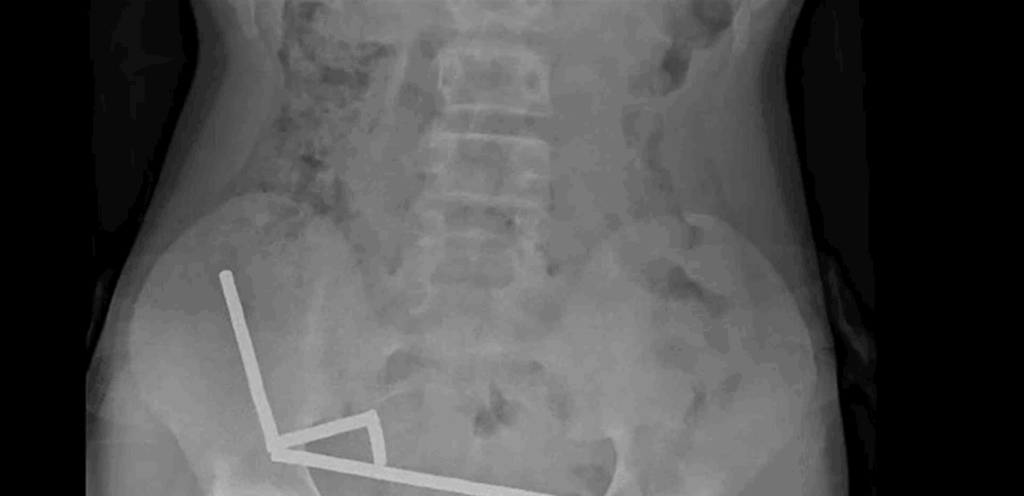

وقال التقرير أن الطفل “أكد أنه ابتلع ما يقرب من 80-100 مغناطيس عالي الطاقة (نيوديميوم) بأبعاد 5x2 مم قبل حوالي أسبوع“. وأضافوا أن المغناطيسات، التي حُظرت في نيوزيلندا منذ يناير 2013، تم شراؤها من منصة التسوق الإلكترونية تيمو. وأظهرت الأشعة السينية أن المغناطيسات قد تكتلت معًا في أربعة خطوط مستقيمة داخل أمعاء الطفل.

وشرح التقرير: “يبدو أن هذه المغناطيسات كانت في أجزاء منفصلة من الأمعاء ملتصقة ببعضها البعض بسبب القوى المغناطيسية“. كما أفاد الأطباء بأن ضغط المغناطيس تسبب في نخر (موت الأنسجة) في أربع مناطق من الأمعاء الدقيقة والأعور (جزء من الأمعاء الغليظة) للصبي.